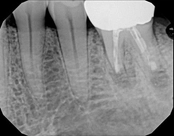

Missed canals and sclerotic orifices/canals:

Before

4-month post-opIn this situation, some would say the canals are so “calcified” that root canal treatment can’t be done; or sometimes the canal can’t be found. And because of that the tooth would need an extraction and an implant. In some instances, root canal therapy can’t be done but that does not mean the tooth is a loss. The solution is micro-apical surgery, an apicoectomy.